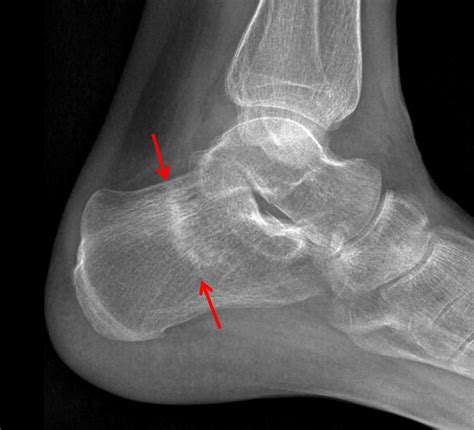

Diagnosing a Stress Fracture Heel

Accurate diagnosis is essential for effective treatment. A healthcare professional will typically perform the following steps to diagnose a stress fracture heel:

• Imaging Tests: X-rays, MRI, or bone scans may be ordered to visualize the fracture and rule out other conditions.